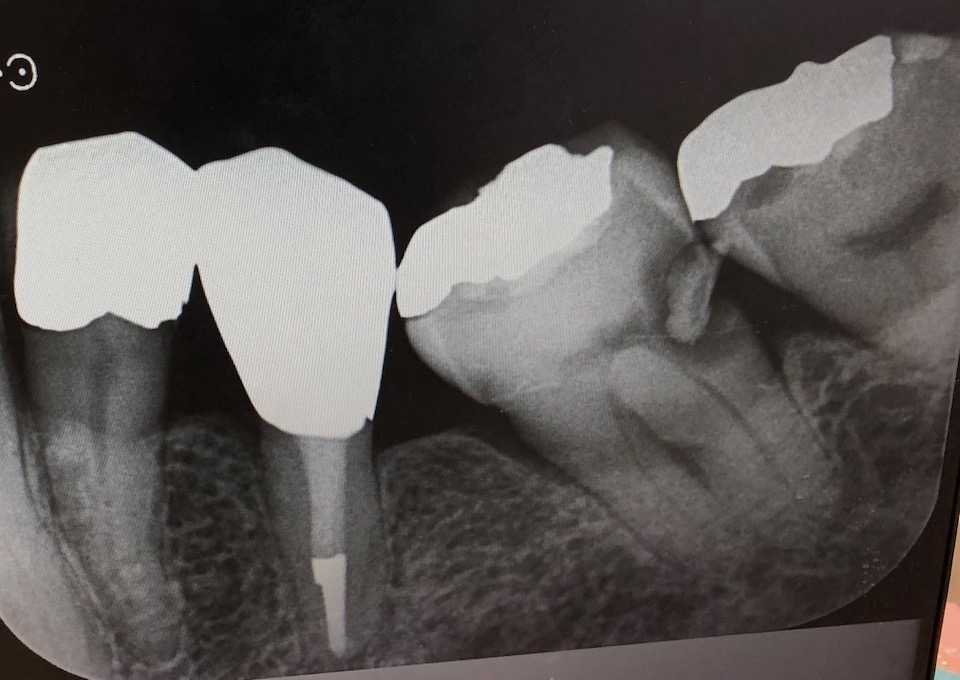

これがうちで撮ったアナログのレントゲン写真。神経に達しているのかそうではないのか、ギリギリと言った風情。充填してあったセメントは亜鉛華ユージノールセメントだった。歯髄鎮静作用があると言われているが、僕にはよく分からない。CRの硬化阻害作用があるので除去するしかないが、露髄させそうで難しかった。セメント除去にほとんどの時間を費やした。